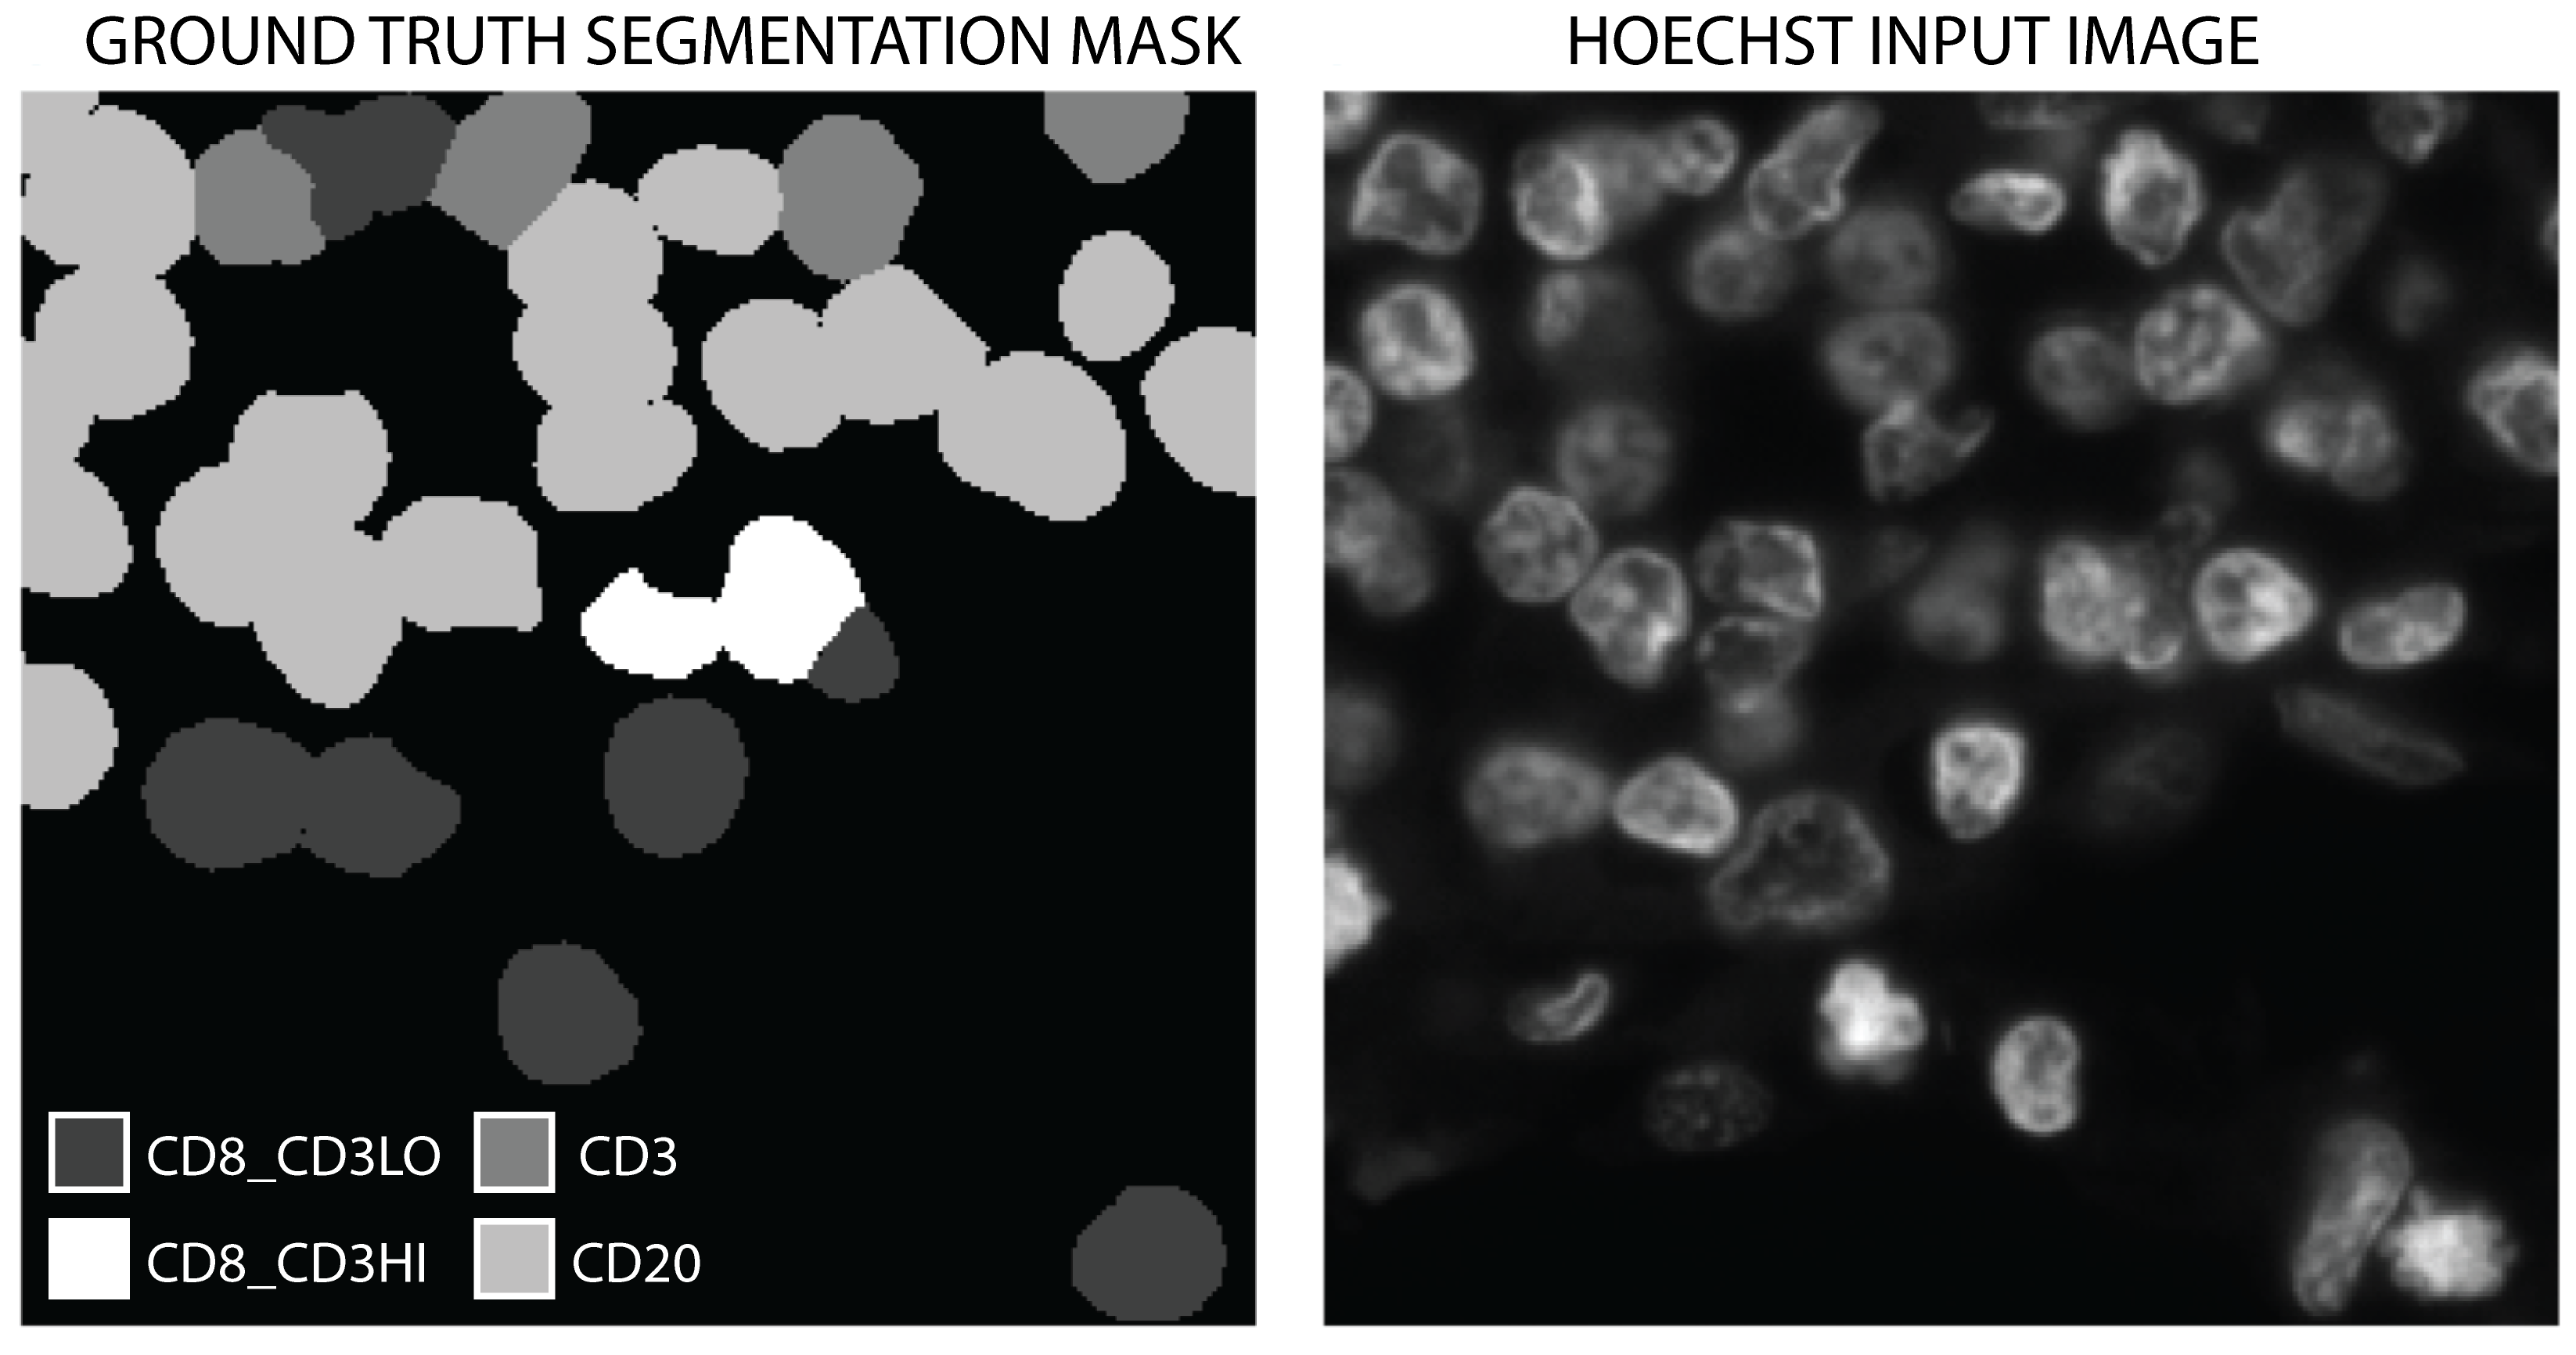

Our data comprised six Whole Slide Images (WSIs) taken from lung cancer biopsies. These were imaged using Hoechst 33342, and also using multiplex immunofluorescence targeting CD3, CD8 and CD20 expressing immune cells, with a Zeiss Zen Axioscan scanner. We then used an established intensity-based classification technique [25] to identify and label cells expressing these proteins in the multiplex immunofluoresence images, the results of which we quality controlled by direct visual inspection to ensure label accuracy. To handle varying levels of co-expression within CD3 and CD8 expressing cells we used a labelling threshold to classify each cell into one of five groups based on protein expression: CD3 only; CD8 and low CD3 (labelled CD8_CD3LO); CD8 and high CD3 (labelled CD8_CD3HI); CD20 only; and background/other. We used these labels to create segmentation maps, which we paired with the Hoechst images, as in Figure 1.

We extracted 7413 pixel patches with a 50% overlap from the Hoechst 33342 stained slides at full resolution, and paired them with the per-pixel class labels from the immunofluorescence intensity classifier as shown in figure 1. Each Hoechst patch was normalised individually, and the total dataset split into training, validation and testing subsets with ratio 80:10:10, providing 5930 training samples, 741 validation samples, and 742 test samples. We also tested training the model on five of the six slides, retaining the the sixth as a holdout test set in order to ascertain the generalisation ability, and found no decrease in performance.